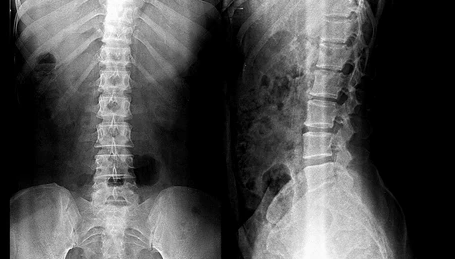

Una de las ventajas que ofrece este equipo a nuestros pacientes es la mínima exposición a

radiaciones, pues al ser digital la cantidad de radiación es mucho menor que en los equipos

tradicionales.

Esto representa también un gran beneficio en la realización de estudios radiológicos

pediátricos.